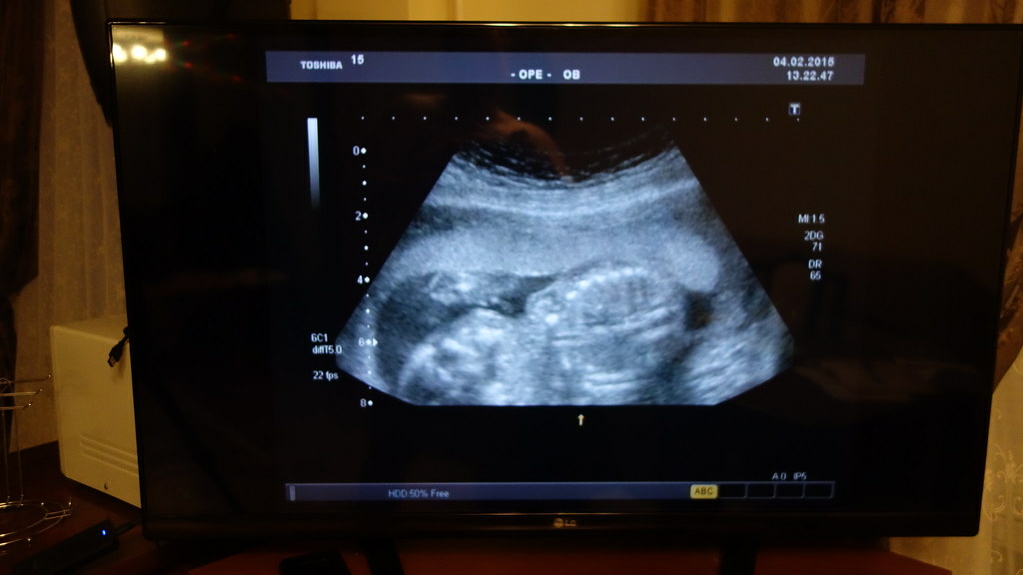

Запорожская область. Ситуация с кадрами в здравоохранении Запорожской области остается критической. Особенно остро ощущается нехватка врачей ультразвуковой диагностики.

По данным областного Минздрава, при необходимом штате в 37 специалистов, на местах работают всего 11. Таким образом, укомплектованность этим ключевым персоналом едва превышает 29%.

Прямым следствием кадрового голода стало значительное увеличение времени ожидания диагностики. В государственных медучреждениях запись на УЗИ растянулась от нескольких суток до двух недель. Исключение составляют лишь экстренные случаи, когда исследование проводят без задержек.